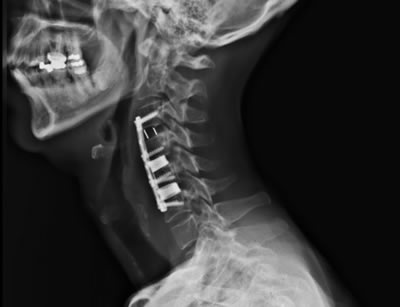

IMÁGENES

Galería de imágenes